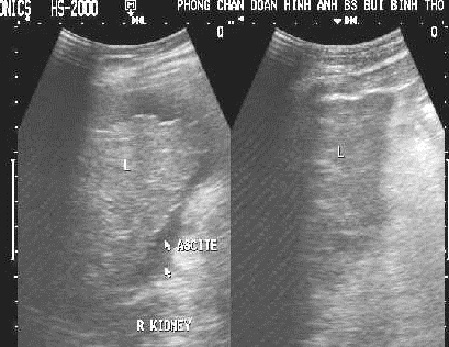

Images echographiques cirrhose du foie a la periode

d'etat : Foie a petit

volume , bord irregulie , angle anterieure a obtu - Ascite au espace

Morrisson et region sous hepatique droit . |